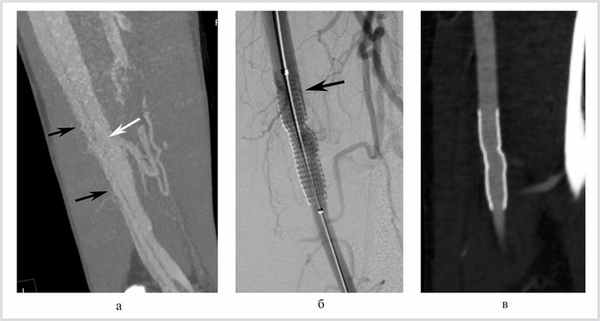

При наличии рубцовых изменений, когда диаметр проксимального отдела артерии имеет больший диаметр, чем область соустья, возможно использование эндопротезов, не полностью прилегающих к стенкам артерии до свища. После прекращения артериовенозного сброса происходит ремоделирование сосуда (уменьшается диаметр проксимального участка и увеличивается диаметр дистального участка артерии), благодаря чему стент-графт плотно прилегает к стенкам сосуда (рис. 1).

Рис. 1. Травматический артериовенозный свищ бедренной артерии со сбросом крови в бедренную вену. Эндопротезирование бедренной артерии.

В случае отсутствия рубцового перипроцесса возможно недостаточно плотное прилегание самораскрывающегося стент-графта к стенке сосуда с сохранением артериовенозного сброса, что потребовало в одном наблюдении дополнительной имплантации в эндопротез самораскрывающегося стента большего диаметра [8].

Тромбоз самораскрывающихся эндопротезов, установленных в бедренную артерию и в переднюю большеберцовую артерию (рис. 2), отмечался в 2 наблюдениях в сроки до 2 нед, что, однако, не привело к ухудшению состояния больных и не потребовало дополнительного лечения, симптоматика регрессировала вследствие ликвидации артериовенозного сброса. Это объясняется тем, что артериовенозный сброс оказывает большее влияние на гемодинамику конечности, чем окклюзия артерии, и при его длительном существовании развивается богатая сеть коллатералей.

Рис. 2. Травматический артериовенозный свищ передней большеберцовой артерии со сбросом в переднюю большеберцовую вену. Эндопротезирование передней большеберцовой артерии.